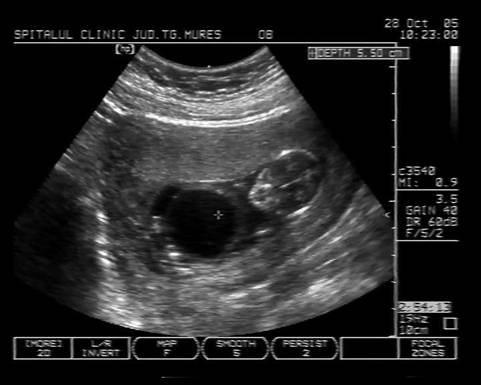

Fig. nr.125 Omfalocel la o sarcina de 12 saptamani ( zona anecogena marcata cu caliper )

Fig. nr.126 Acelasi fat ca in figura precedenta, sectiune transversala abdominala, cu ecou Doppler la periferia omfalocelului